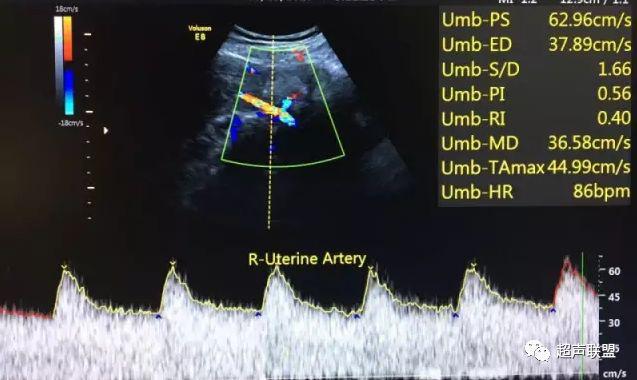

5 子宫动脉血流测定

正常妊娠时血流速度增加,血流阻力下降。缺氧早期的血流再分配,子宫动脉血流RI、PI值增加,阻力指数(RI)>0.57,子宫动脉血流频谱出现切迹。

3、子宫动脉标准:孕26或27周后,子宫动脉S/D>2.7,(RI)>0.57,有舒张早期切迹;

图7 正常中孕期子宫动脉频谱

图8 胎儿宫内缺氧,子宫动脉舒张早期可见切迹